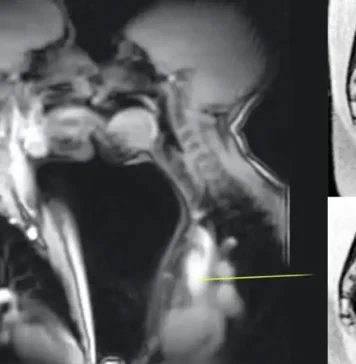

എം.ആർ.ഐ സ്കാനറിനുള്ളിൽ ദമ്പതികളുടെ ലൈം#ഗികബന്ധം; ശരീരശാസ്ത്രത്തെ മാറ്റിയെഴുതിയ വിചിത്രമായ പരീക്ഷണം

ദാമ്പത്യജീവിതത്തിൽ പുതുമകൾ കൊണ്ടുവരാൻ ആഗ്രഹിക്കുന്ന ദമ്പതികൾ പലപ്പോഴും യാത്രകളോ പുതിയ രീതികളോ പരീക്ഷിക്കുന്നത് സർവ്വസാധാരണമാണ്. കാമസൂത്രയിലെ അധ്യായങ്ങൾ മറിച്ചുനോക്കുന്നവർ മുതൽ കിടപ്പുമുറിയിലെ വിരസത മാറ്റാൻ പുതിയ ഇടങ്ങൾ തേടുന്നവർ വരെയുണ്ട്. എന്നാൽ ഒരു...